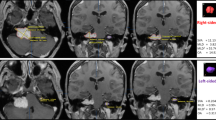

3D tumor masks were created for vestibular schwannomas (unilateral or bilateral) as follows (Fig. 2):

To highlight the vestibular schwannomas, a thresholding algorithm was used on selected slices containing the tumor mass. A ‘split regions’ algorithm was used to isolate the tumors and remove the non-tumorous voxels. Consideration was taken with voxels lining the border of the mask. Missing and surplus voxels were adjusted to include or exclude as necessary using the paint function. After the initial mask creation, the tumors were re-examined in all three planes (coronal, axial, sagittal views) to correct for any missing or extra voxels. All the models were reviewed by a neuroradiologist, who made necessary adjustments.

The ‘volume’ measurement tool was used to calculate the 3D volume (in mm3) of each tumor mask. To visualize the shape, size, and pattern of growth of the masked tumors, a mask was created of the pons at the levels of the tumors.